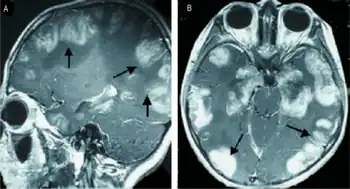

| a,b)MRI scans of the brain show multiple non-homogeneous, hypodense masses along the bilateral cortex | |